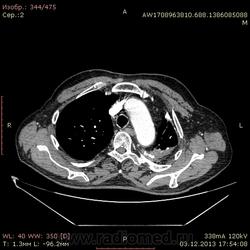

Ребята, вы что, какая жидкость? Чистая известь, посмотрите в костном окне. Отставить натив (в данном случае, хотя для аневризм он обычно нужен). Отставить тромбоз верхней полой вены (потоковые артефакты, не дело вены в артериальную фазу оценивать). Отставить аневризму  аорты, поперчник восходящего отдела на уровне легочного ствола 42мм. А вот легочная гипертензия, здравствуй: поперечник легочного ствола - 37мм, ПЛА - 25мм, ЛЛА - 25мм, НАо - 25-34мм.

В анамнезе перенёс туберкулёз неизвестной давности.

Кальцификация плевральных листков  является неотъемлемой частью развития хилезоподобных выпотов в результате длительности процесса (  в среднем сроки появления кальцинации около 5 лет), как следствие порпажения серозных оболочек.

ПСЕВДОХИЛОТОРАКС

Две различных ситуации могут привести к высокому содержанию жиров в плевральной жидкости: 1) повреждение грудного лимфатического протока и его главных ветвей, приводящее к попаданию лимфы в плевральную полость и образованию хилоторакса; 2) накопление большого количества холестерина или лецитин-глобулиновых комплексов в длительно существующем плевральном выпоте, приводящее к псевдохилотораксу. Эти два состояния необходимо четко дифференцировать, так как их этиология и лечение абсолютно различны. Псевдохилоторакс является еще более редким состоянием, чем хилоторакс, в литературе описано около 200 случаев.

Плевральные поверхности у большинства больных заметно утолщены, иногда с кальцификацией, время существования плеврального выпота более 5 лет. В этом случае плевра насыщается холестерином, так как во время активного воспаления повышается его фильтрация в плевральную полость. Источником холестерина могут стать гибнущие эритроциты и лейкоциты. Утолщенная плевра ингибирует выведение холестерина из плевральной полости. Основными причинами псевдохилоторакса являются туберкулезный плеврит (54%) и хронический ревматоидный плеврит (9%). Изредка он может быть ассоциирован с травмой или хирургическим вмешательством. Диагноз ставится на основании исследования плевральной жидкости. После центрифугирования супернатант выпота не становится прозрачным, у большинства больных в осадке определяют кристаллы холестерина характерной ромбовидной формы и повышенный уровень холестерина в выпоте (>6,45 ммоль/л). КТ может выявить жировые наложения и утолщение плевры. Лечение псевдохилоторакса должно быть направлено на лечение вызвавшего его заболевания (в основном туберкулеза). При выраженных дыхательных нарушениях и большом объеме выпота показаны плевральная пункция и дренирование, хотя их выполнение усложняется утолщенной плеврой и отрицательным внутриплевральным давлением